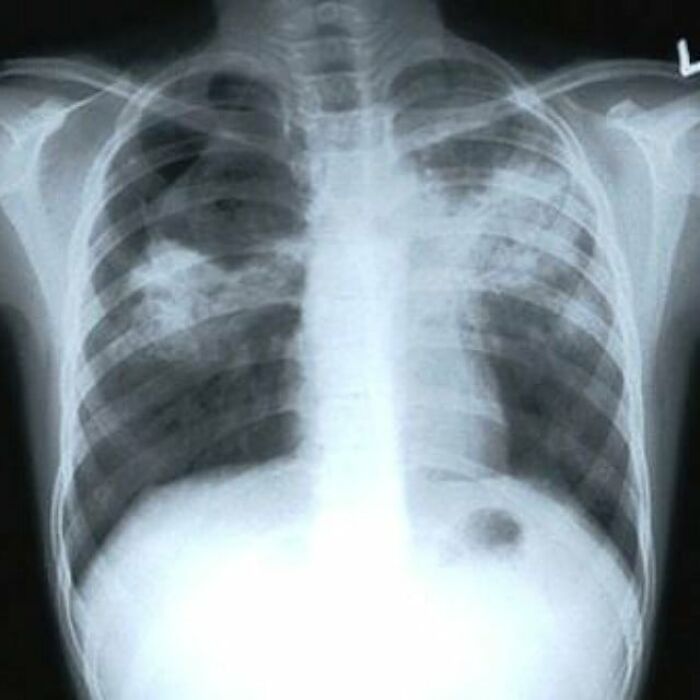

Cross Section Of The Lungs Of A Patient With Copd (Emphysema , Chronic Bronchitis And Asthma)